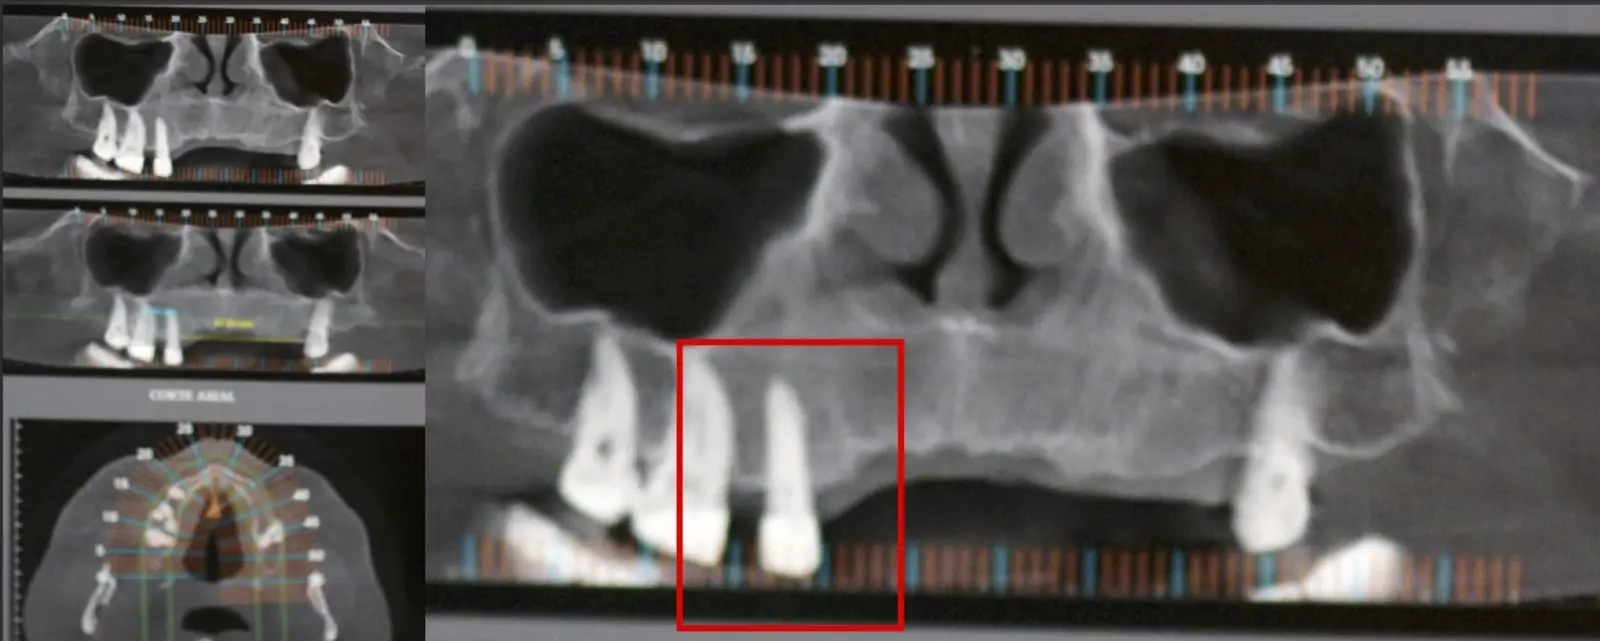

El origen puede ser bacteriano (colonias bacterianas persistentes4, patología periodontal asociada5, reinfecciones por falta de sellado coronal), mecánico (preparación deficiente, fractura de instrumentos, fracturas radiculares6, extravasación de material de obturación7 con ó sin compromiso de estructuras vecinas) y anatómico (conductos accesorios poco permeables o calcificados)8 (Figuras 1 - 4).

La microcirugía endodóntica apical busca conservar la mayor cantidad de longitud de raíz y de hueso circundante sano para no afectar la estabilidad de la pieza.11 Por ello, es ideal el uso de microscopios, elementos de magnificación, instrumental específico (insertos de ultrasonido endodónticos) y materiales de sellado eficientes para el tratamiento retrogrado. Su éxito es alto y evidencia una cicatrización ósea completa en el 74% de los casos al año de tratamiento.12 Cabe destacar que este logro está asociado también, a predictores propios de cada paciente, como la edad, tipo de pieza, profundidad de sondaje y extensión de la lesión.1 El uso complementario de la tomografía computarizada es resaltante como el instrumento imagenológico de elección para la etapa de planificación microquirúrgica,13 ya sea para una ejecución a mano alzada o con guías prefabricadas.14,15